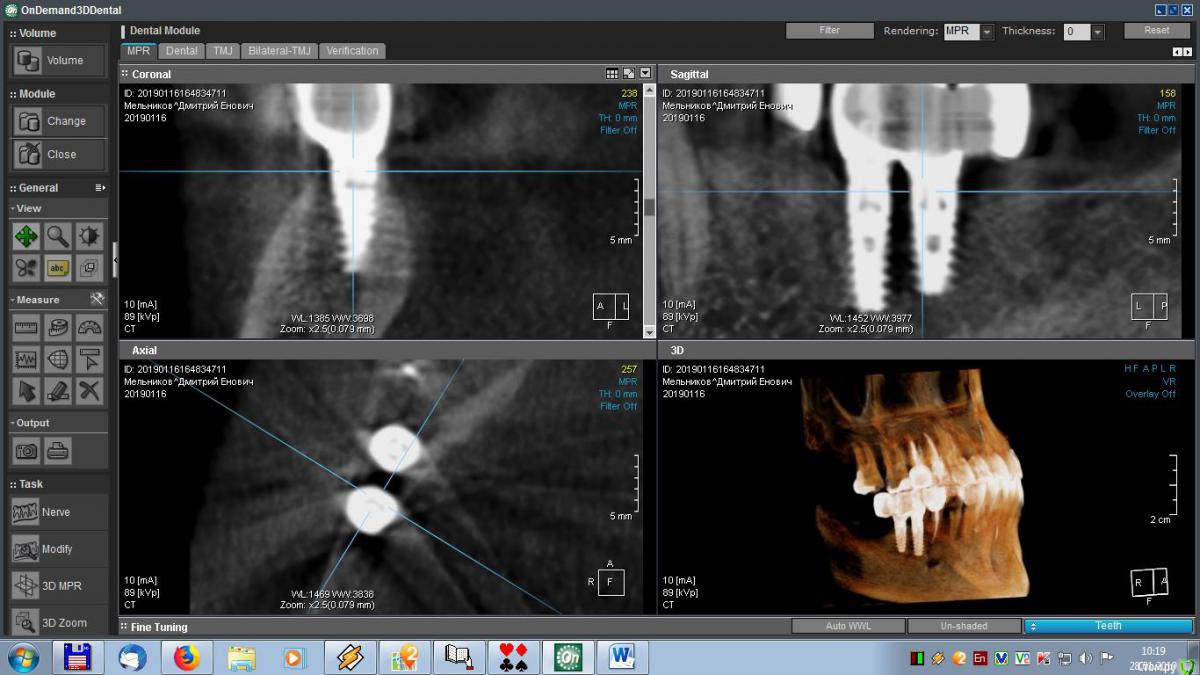

meld Опубликовано 29 января, 2019 Автор Поделиться Опубликовано 29 января, 2019 Здравствуйте, уважаемые доктора! Скоро год, как мне поставили метало-керамические коронки. До сих пор я ощущаю зуд в области имплантатов. На контрольном приеме врач ничего криминального не увидел, прописал чистку, фотосан и КТ, Я все сделал, по КТ врач сказал, что все нормально. Посмотрите, пожалуйста, мои среза и подтвердите (или нет) - все ли нормально. Спасибо. Ссылка на комментарий

meld Опубликовано 29 января, 2019 Автор Поделиться Опубликовано 29 января, 2019 Выложил больше срезов. Спасибо. Ссылка на комментарий